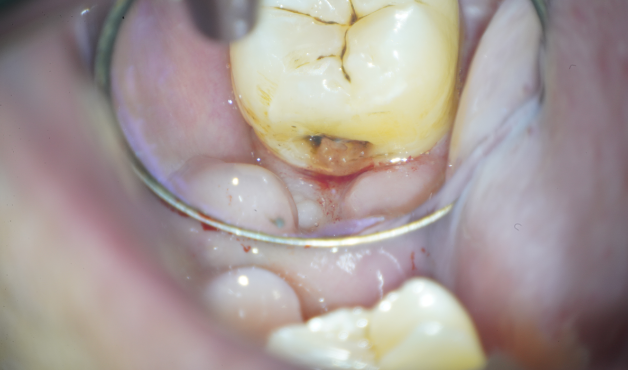

ダイレクトレストレーションによる

低侵襲な虫歯治療を行った症例

Before

Under treatment

After

主訴

虫歯の治療をして欲しい

治療内容

ダイレクトレストレーション

治療費用

55,000

治療の

リスク

経年的に材質が変色してくる可能性があります。